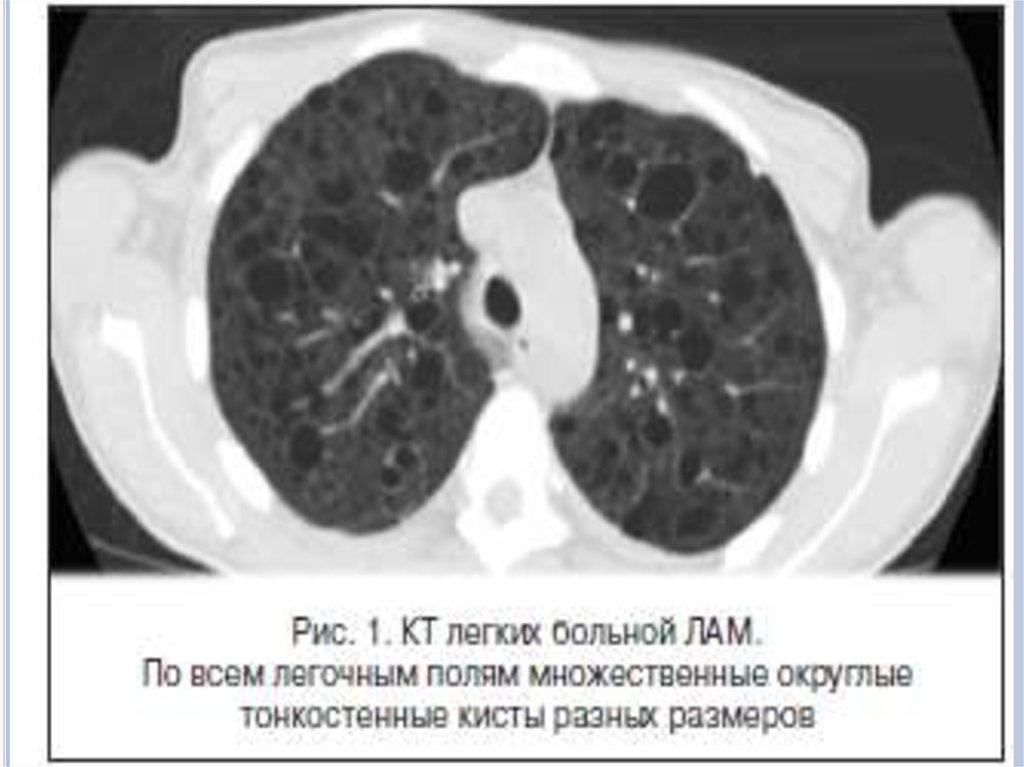

Инструментальные методы исследования

Наиболее характерный морфологический признак ЛАМ кистозная трансформация легких, которая обычно выявляется

на компьютерных томограммах. Кисты бывают двух типов:

мелкие множественные типа «сотового легкого» и

крупные кисты, присущие буллезной эмфиземе.

Толщина стенки кисты не превышает 2 мм, причем стенка

кисты выявляется не всегда и не на всем протяжении.

Окружающая легочная ткань часто не изменена. Однако

сочетание фиброзных и кистозных изменений не

противоречит диагнозу ЛАМ. Таким образом,

рентгенологическая картина ЛАМ не патогномонична.

Компьютерная томография легких. Для ЛАМ

характерны множественные диффузные, хорошо очерченные

мелкие тонкостенные кисты. Кисты при этом заболевании

значительно отличаются от зон центрилобулярной эмфиземы

легких, которые не имеют четких границ и своих собственных

стенок, а также от фиброзирующего альвеолита, при котором

основные изменения расположены по периферии легких,

имеются поля фиброза и дезорганизации паренхимы легких,

а кисты расположены субплеврально и

характеризуются довольно толстыми стенками.

Данные компьютерной томографии настолько специфичны

для ЛАМ, что некоторые авторы для постановки точного

диагноза полагают достаточным заключение компьютерной

томографии (КТ) без проведения биопсии легких.